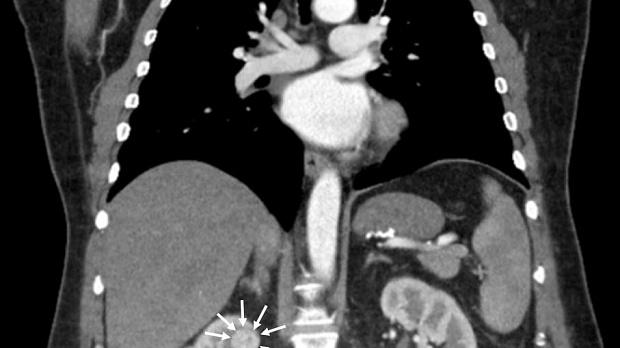

Иллюстрация №7: Рис. 6. Компьютерная томография в МГОБ № 62: стрелочками показана опухоль правой почки.

По данным компьютерной томографии органов грудной клетки и брюшной полости с контрастным усилением: состояние после гастрошунтирующей операции, умеренно выраженная внутрибрюшная и забрюшинная лимфаденопатия (лимфоузлы до 10 мм), в верхнем полюсе правой почки опухоль до двух сантиметров в диаметре (рис. 6).

На основании жалоб, анамнеза, данных осмотра и обследований был сформулирован предварительный диагноз: "Первично-множественное синхронное злокачественное заболевание: 1) рак кардиального отдела желудка, стадия I, сT1N0M0, Siewert II. Гастрошунтирующая операция по поводу морбидного ожирения от 10.06.2019г. (центр бариатрической хирургии); 2) рак правой почки, стадия I, сT1аN0M0".